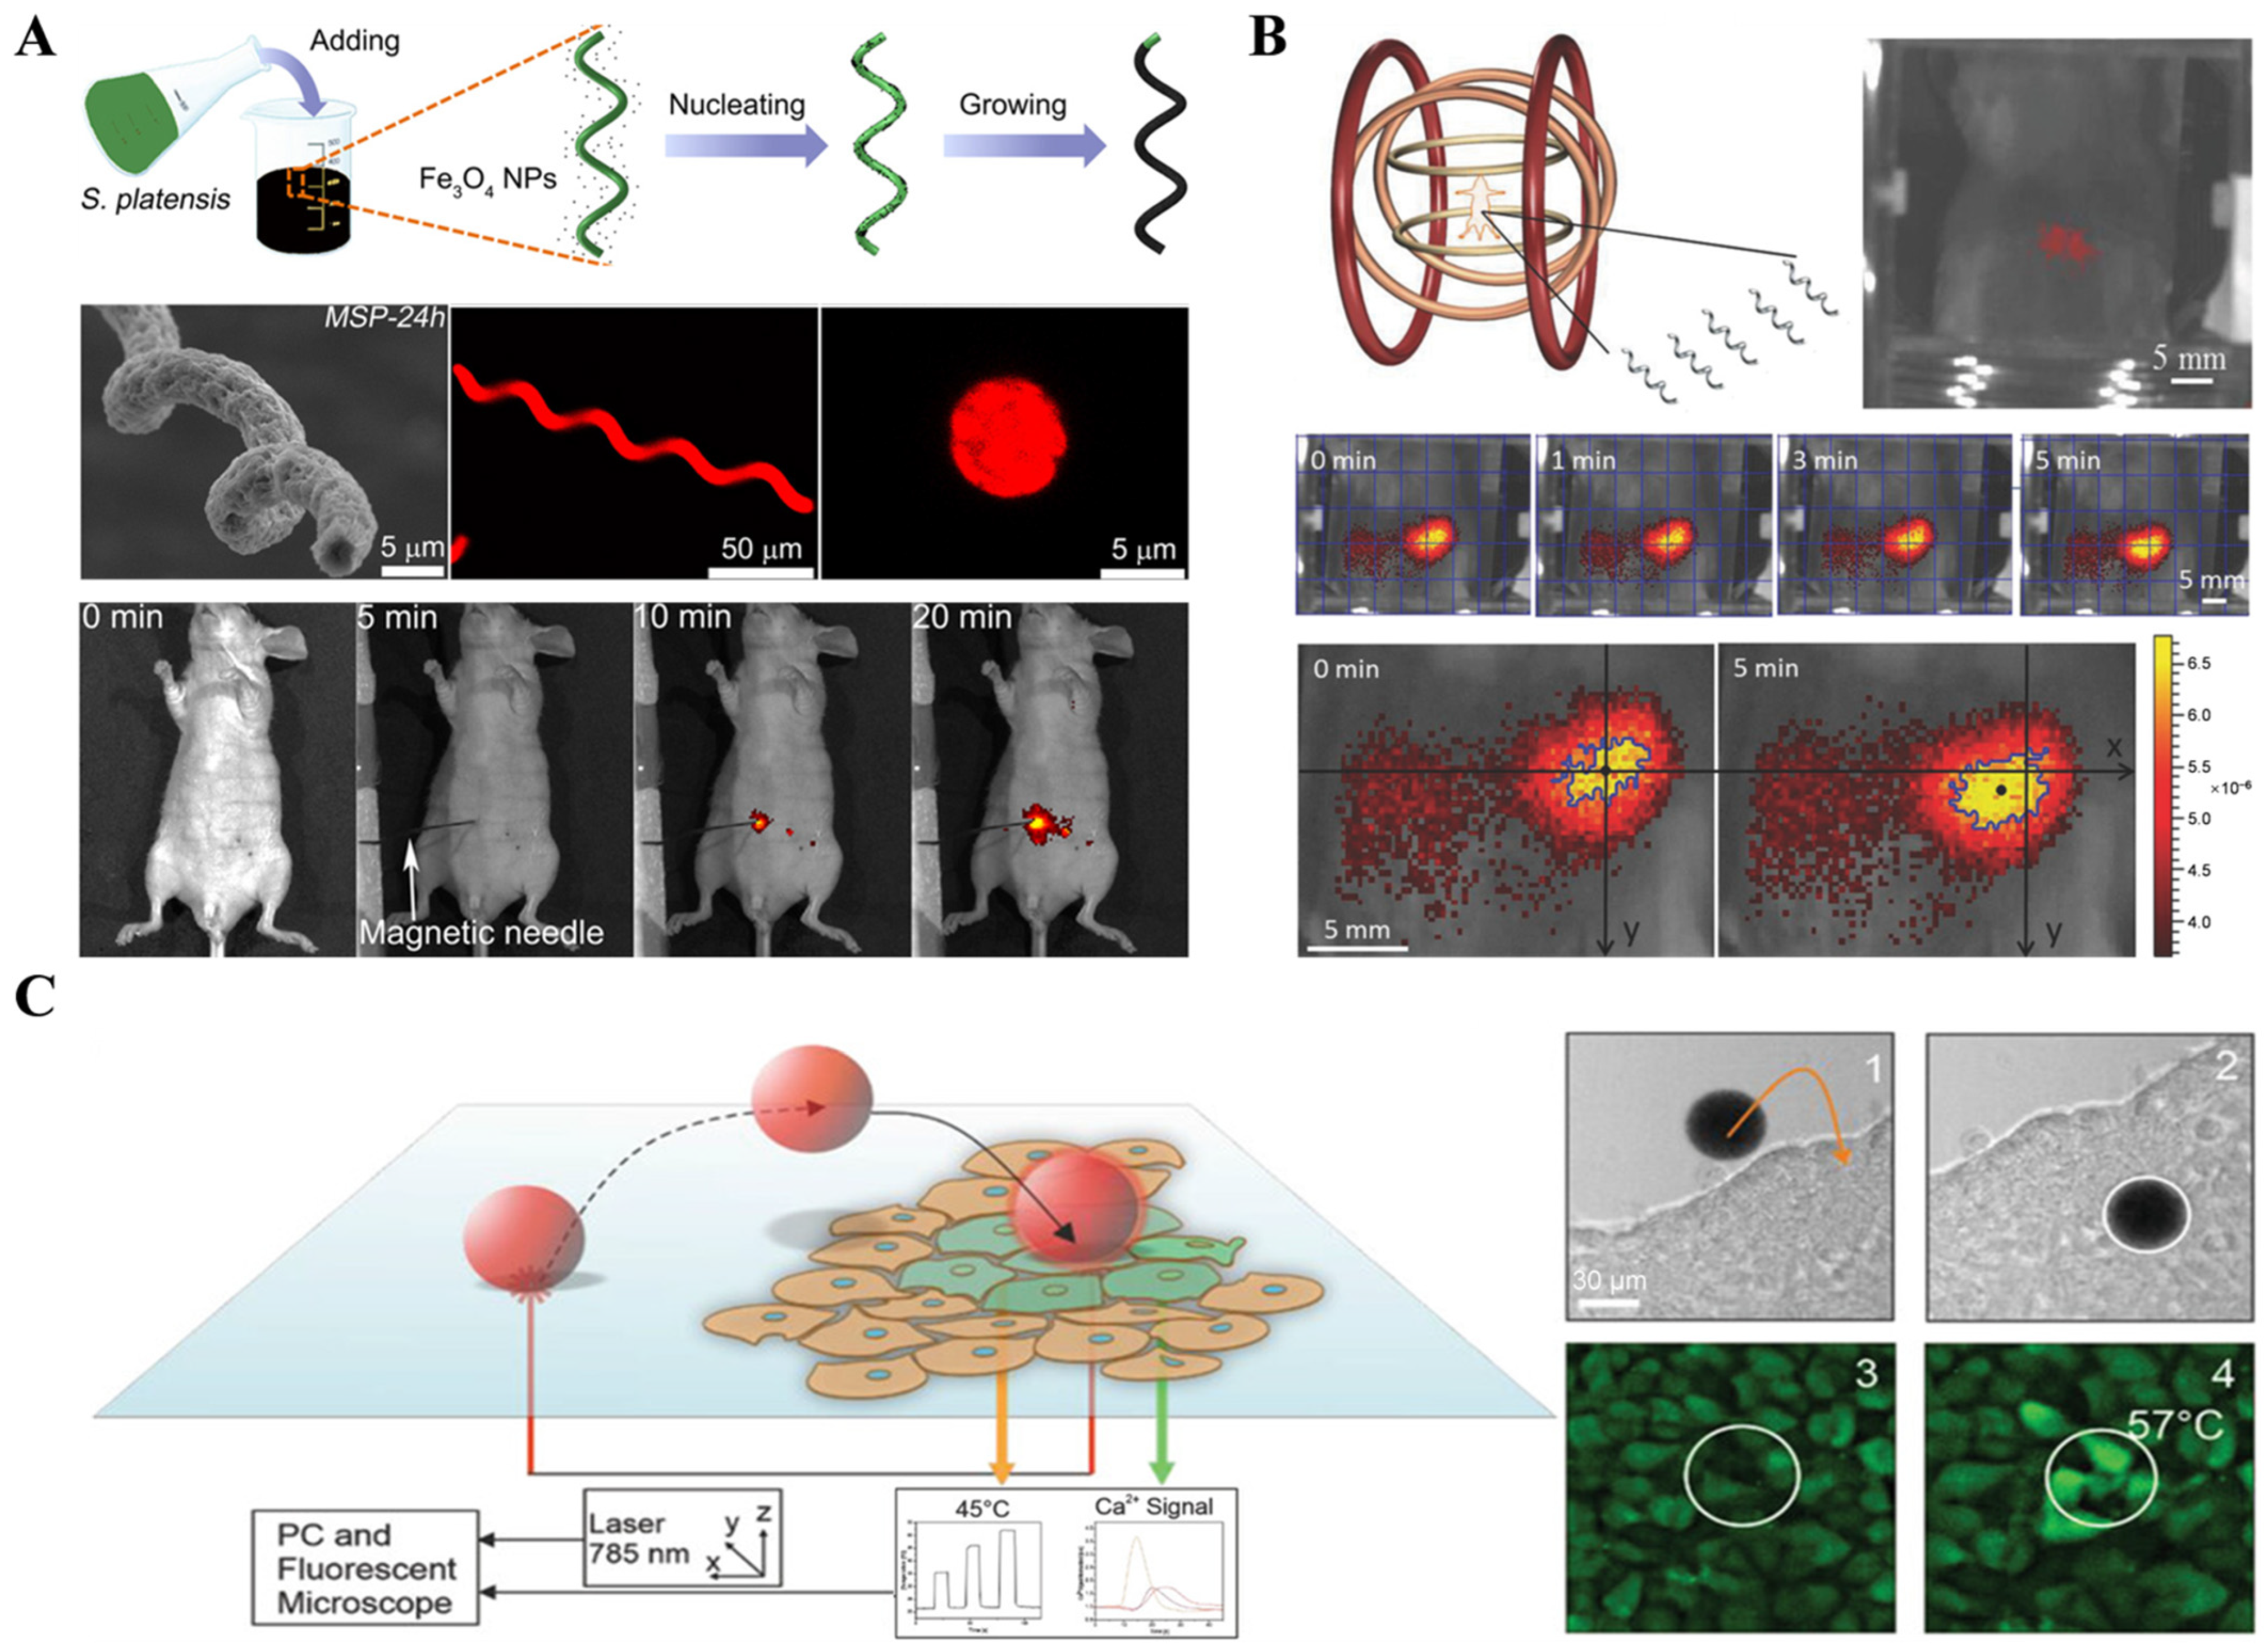

2.1.1. Fluorescence Imaging Technology

2.5.2. Magnetomotive Assisted Imaging

- Harder, P.; Iyisan, N.; Wang, C.; Kohler, F.; Neb, I.; Lahm, H.; Dressen, M.; Krane, M.; Dietz, H.; Oezkale, B. A Laser Driven Microrobot for Thermal Stimulation of Single Cells. Adv. Healthc. Mater. 2023, 12, e2300904. [Google Scholar] [CrossRef] [PubMed]